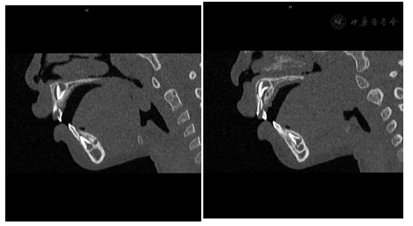

点击查看大图

图2

CT图像 MPR显示右侧中切牙中间断裂